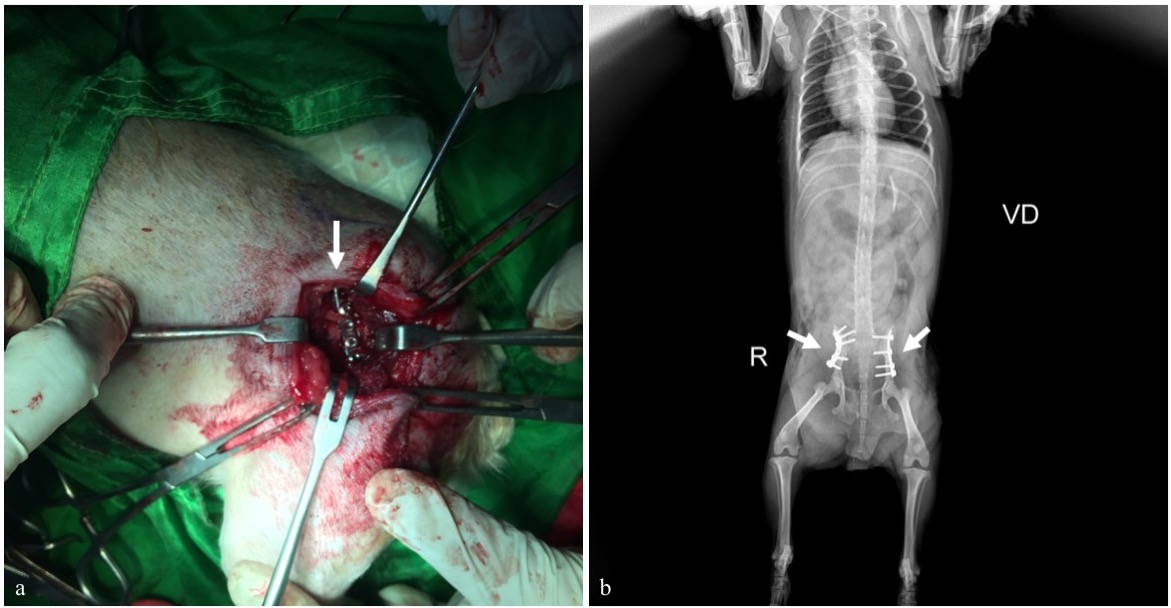

Fraktur adalah terputusnya kontinuitas jaringan tulang yang umumnya disebabkan oleh trauma. Anjing ras Yorkshire berumur 2,8 tahun dengan bobot badan 2,6 kg menunjukkan gejala klinis tidak bisa berdiri, kedua ekstremitas posterior mengalami diplegic lameness dan anjing hanya bertumpu dengan ekstremitas anterior. Anamnesis dengan pemilik hewan mengatakan anjingnya mengalami trauma akibat tertimpa tangga. Hasil pemeriksaan radiografi dengan posisi hewan right lateral dan ventro dorsal menunjukkan fraktur bilateral pelvis berbentuk oblique pada tulang ilium. Penanganan yang dilakukan adalah dengan metode open reduction internal fixation menggunakan bone plate 2.0 veterinary cuttable plate (VCP) dengan screw 2.0 mm cortical non-self-tapping pada kedua sisi tulang ilium. Hari ke-3 setelah tindakan bedah, pasien mulai dibantu untuk berjalan sebagai upaya melatih pergerakan ekstremitas posterior. Satu minggu setelah bedah, pasien sudah bisa berjalan dan menunjukkan perkembangan yang baik. Penanganan bilateral fraktur pelvis berbentuk oblique pada bagian ilium dapat ditangani dengan bone plate dan screw.